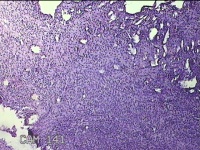

右侧卵巢囊肿

性别

女

年龄

36岁

临床诊断

一般病史

发现双侧附件囊肿1年。

标本名称

大体所见

灰白暗红色囊壁样组织2.5x2x0.3cm一块,表面光滑,部分已切开,囊内容物已流失,囊壁厚0.2cm。

考虑:子宫内膜异位囊肿。